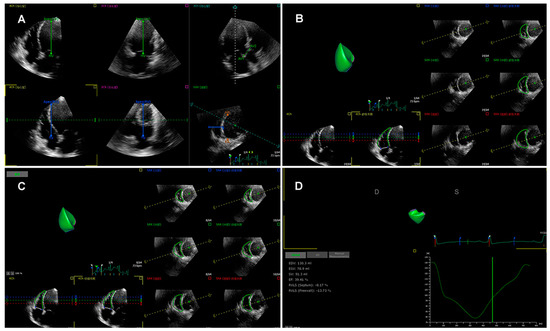

3.3. Three-Dimensional Speckle Tracking Echocardiography

More recently, three-dimensional speckle tracking echocardiography (3D-STE) has been introduced as a novel technique than can track the myocardial motion within the 3D volume. Thus, 3D-STE is free of geometric assumptions and out-of-plane motion of the speckles, allowing a more accurate and comprehensive evaluation of myocardial function owing to overcoming the limitations of 2D-STE [35,38,65,66]. Three-dimensional STE analysis for the right ventricle is shown in Figure 2. Its accuracy and reproducibility in assessing RV function have been confirmed in patients with transplanted hearts, pulmonary hypertension, and hypoplastic left heart syndrome after Fontan palliation [63,67,68,69]. Moreover, we previously investigated the feasibility and accuracy of 3D-STE for the quantification of RVLS in comparison with CMR imaging in a large number of study populations with a wide variety of RVEF and cardiovascular pathologies, and found that the 3D-RVFWLS values correlated better than 2D-RVFWLS values with CMR values (0.85 vs. 0.64) with smaller bias and narrower limits of agreement. Our findings demonstrated the superiority of 3D-RVFWLS over 2D-RVFWLS in evaluating RV function against CMR imaging [70,71]. However, 3D-STE also has several limitations, such as low temporal resolution and dependence on image quality [35,64].

Figure 2. Longitudinal strain of the RV free wall and septum using three-dimensional speckle tracking echocardiography. (A) Setting reference points; (B,C) RV endocardial border tracking; (D) Longitudinal strain of RV free wall and septum were automatically generated.